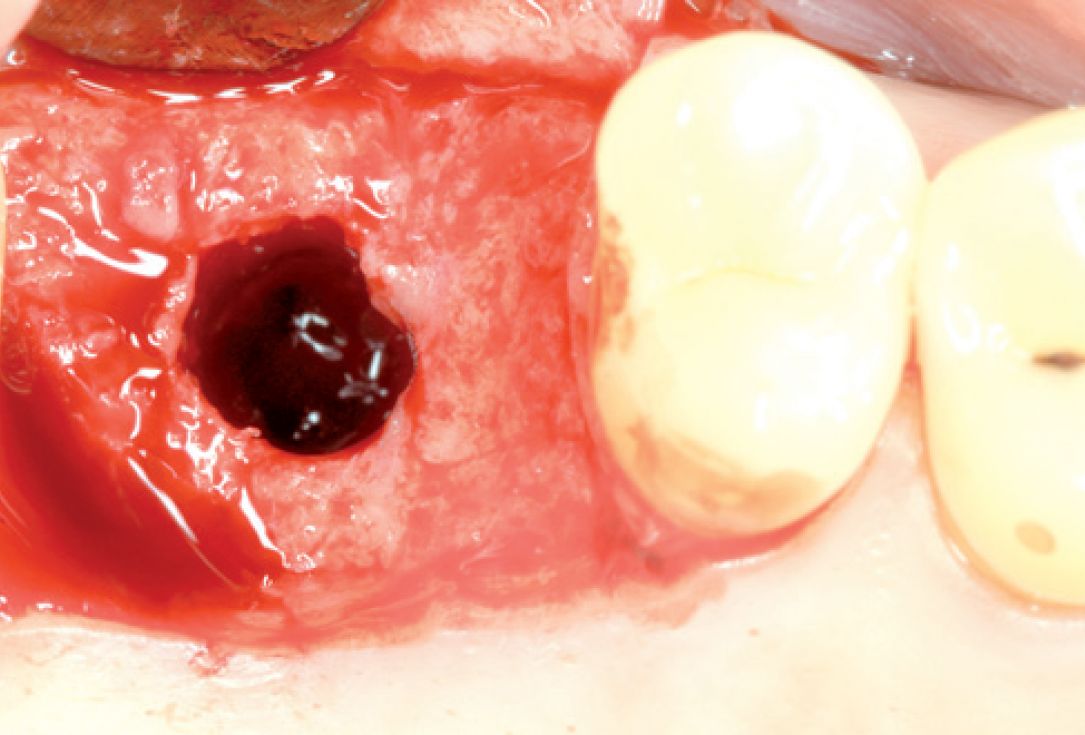

03/10 - Presentation of the soft tissue situation before implantationInternal sinus lift with maxresorb® inject - case Dr. Frank Kistler